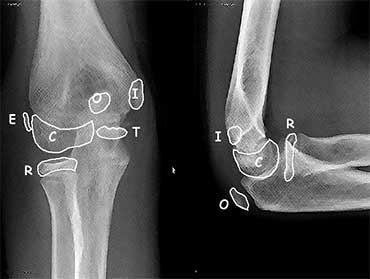

ossification centres around the elbow?